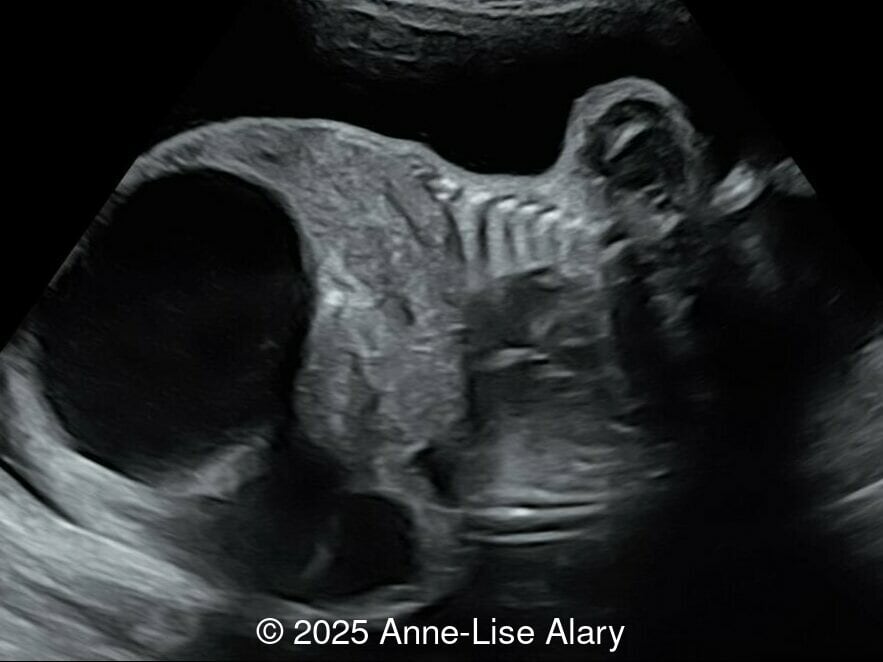

20-year-old primigravid woman, presented late for prenatal care at 29 weeks gestation. There was no consanguinity, and no pertinent past medical or familial history. We found the following anomalies:

Axial image of the abdomen

Image 1 Axial image of the abdomen

Our prenatal ultrasound revealed a male fetus with megabladder, dilation of both ureter and kidneys, and thinned kidney parenchyma consistent with Lower Urinary Tract Obstruction (LUTO).  Additional findings suspected on ultrasound and confirmed on computed tomography included:

The diagnosis of PBS is often made in the second trimester of pregnancy, although it has been described as early as 11 weeks of gestation [20]. The most frequent ultrasound findings are a large, thin-walled bladder accompanied by bilateral hydroureter/hydronephrosis, dysplastic kidneys with echogenic renal parenchyma and renal cortical cysts, and abdominal wall laxity which is better viewed after bladder decompression [21]. Cryptorchidism can be detected prenatally by 28 to 30 weeks gestation when the testes descend into scrotum. There may be a patent urachus, visible as a cystic connection between bladder and umbilicus. Oligohydramnios is a frequent finding, which makes it difficult to visualize the associated anomalies.